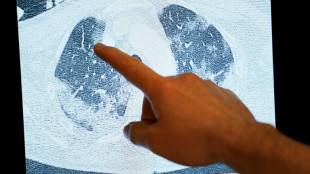

Dois novos estudos dão pistas sobre covid longa

Dois estudos recentes dão pistas sobre as causas da chamada covid longa, uma síndrome regida por mecanismos ainda misteriosos: um trata do efeito conjunto de sequelas em vários órgãos, e o outro, do danos nos neurônios.